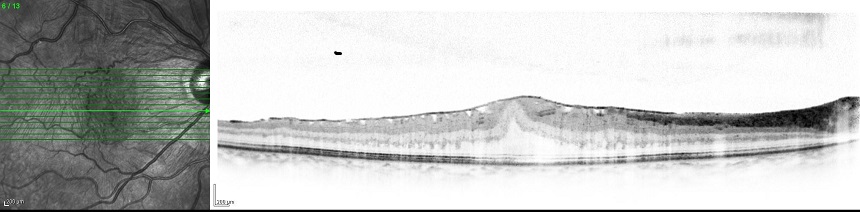

| 黄斑上膜(黄斑前膜)は光沢のあるセロファン膜のように見え、周囲の網膜にしわが形成されている。 |

| 検査 膜の広がりを知るために眼底検査をします。しわの程度や視力に影響する黄斑の変形の程度を評価するために、光干渉断層計(OCT)検査を行います。アムスラーチャートやMチャートと言った、ゆがみの程度を評価する検査もあります。続発性のもの、特にぶどう膜炎に併発するものに対しては、蛍光眼底造影検査を行ない、炎症の活動性を評価することもあります。 |